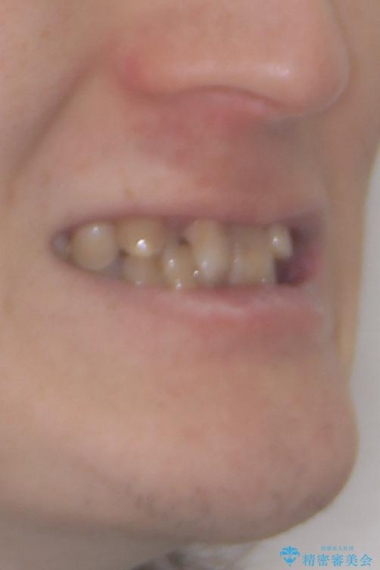

- 上下の前歯のデコボコを改善したいと来院された患者様です。

上顎の歯列幅が狭く、それによって歯が並ぶスペースが不足しています。

また下顎の歯列幅も制限され、内側に歯が倒れています。

それらを改善するため上顎に拡大装置を用いて、審美装置にてワイヤー矯正を行いました。

左上の乳犬歯は当初保存する計画でしたが、虫歯が大きいため抜歯になり、患者様の希望によりブリッジにしました。

上顎が側方に拡大されて歯が並ぶスペースを確保できました。

それに伴い下顎の歯列も拡大され、舌側に倒れているのが改善されました。